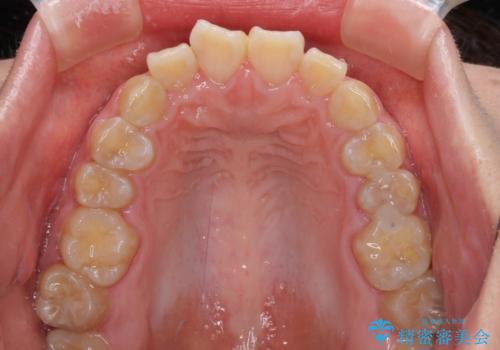

- クリアブラケット

- 2年4ヶ月

- 口元の閉じにくさと、前歯のでこぼこの歯並びを気にして来院された患者様です。

口元を積極的に引っ込めるために、上下左右の小臼歯計4本を抜歯することとしました。

4本の歯を抜歯したことで、飛び出していた口元が引っ込み、横顔が大きく改善されました。